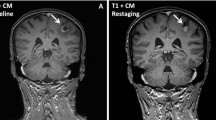

In contrast to normal brain, experimental brain metastases exhibited variable and generally elevated 14C- lapatinib concentrations which ranged from 100 to 2,890 ng/g at 2 h and from 8 to 1,300 ng/g at 12 h after oral dosing. Figure 1 presents representative images of 14C-lapatinib distribution in brain metastases. In most cases, 14C-lapatinib concentration significantly exceeded that in surrounding brain tissue (P < 0.05). On average, brain metastasis lapatinib concentration was 7-fold greater than normal brain at 2 h and 9-fold greater at 12 h (Table I ). By 12 h, the brain metastasis/plasma concentration ratio equaled 26%, indicating marked uptake over residual vascular drug (0.7%) (30).

14C-Lapatinib in brain and brain metastases at 2 (a–c) and 12 (d–f) hours following 14C-lapatinib administration (100 mg/kg, p.o.) in mice with 231-BR-HER2 tumors. Representative coronal brain sections showing green EGFP metastasis fluorescence (a,d), Texas Red 3kD dextran fluorescence (b,e), and 14C-lapatinib radioactivity (c,f) from an animal with 231-BR-HER2 brain metastases that received 14C-lapatinib for 2 (a–c) or 12 (d–f) hours. Met = metastasis.

Many brain metastases with elevated 14C-lapatinib also showed increased BTB permeability to Texas Red 3 kDa dextran, as illustrated in Fig. 1. Because compromised BTB integrity may allow greater 14C-lapatinib uptake, a correlation was performed between 14C-lapatinib concentration and Texas Red dextran permeability for n = 160 brain metastases. 14C-Lapatinib was found to correlate significantly with BTB permeability (r2 = 0.27, P < 0.001) (Fig. 2c), consistent with a role of altered BTB integrity in enhanced lapatinib uptake. In contrast, only a weak correlation (r2 = 0.03) was found with metastasis size (mm2)(Fig. 2d). A number of small micrometastases (<1 mm diameter) were found with markedly elevated lapatinib concentration (>10–20-fold). Similarly, a number of large metastases (>1–2 mm diameter) showed only limited lapatinib accumulation (<5–6-fold). Thus, the data differ from prior studies which suggested that BTB permeability may increase directly with tumor size (32,33). In our study, a small subset (<20%) of both small and large brain metastases exhibited marked (>10-fold) lapatinib accumulation which correlated with compromised BTB integrity.